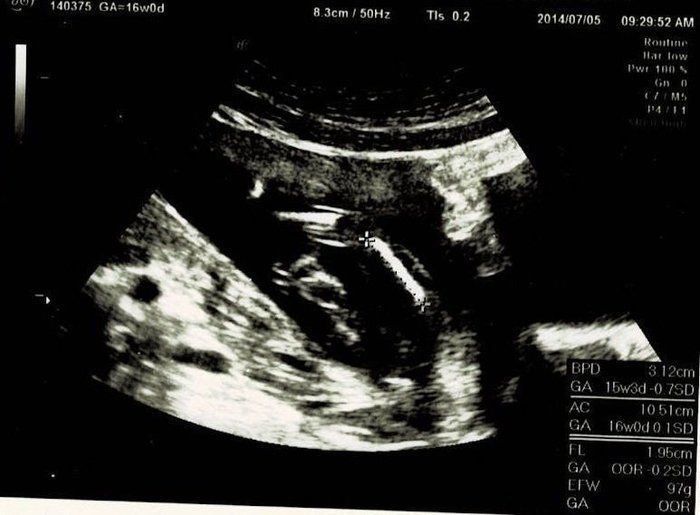

宮本真知さんの妊娠16週目のエコー写真

初めての3Dエコーでした。今までレントゲンのようなエコー写真でしか赤ちゃんを見ていなかったので、芋虫みたいな見た目でも、「ちゃんと人間だ!」と不思議な気持ちになりました。エコーを見るたびに、「本当に人間ができているんだなぁ」と、毎回特別な気持ちになります。3Dエコーは、なんとなくこちらを見ている感じがして、かわいらしいと思ったり。手を口元に寄せて、すでに赤ちゃんらしい丸っこいポーズをしています。

この日は、BPD(頭の左右幅)、AC(おなかの周りの長さ)、FL(太ももの骨の長さ)を測って、赤ちゃんの育ちぐあいを見てくれました。このエコーは足の骨を測っているところです。足の指らしき骨も見えます。先生がスムーズに赤ちゃんの頭やおなか、足を探すのが面白く、測っている最中のエコーもずっと眺めていました。